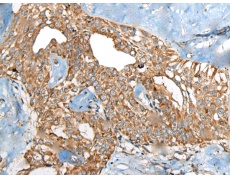

IHC positive control: |

Human thyroid cancer |

IHC Recommend dilution: |

50-300 |